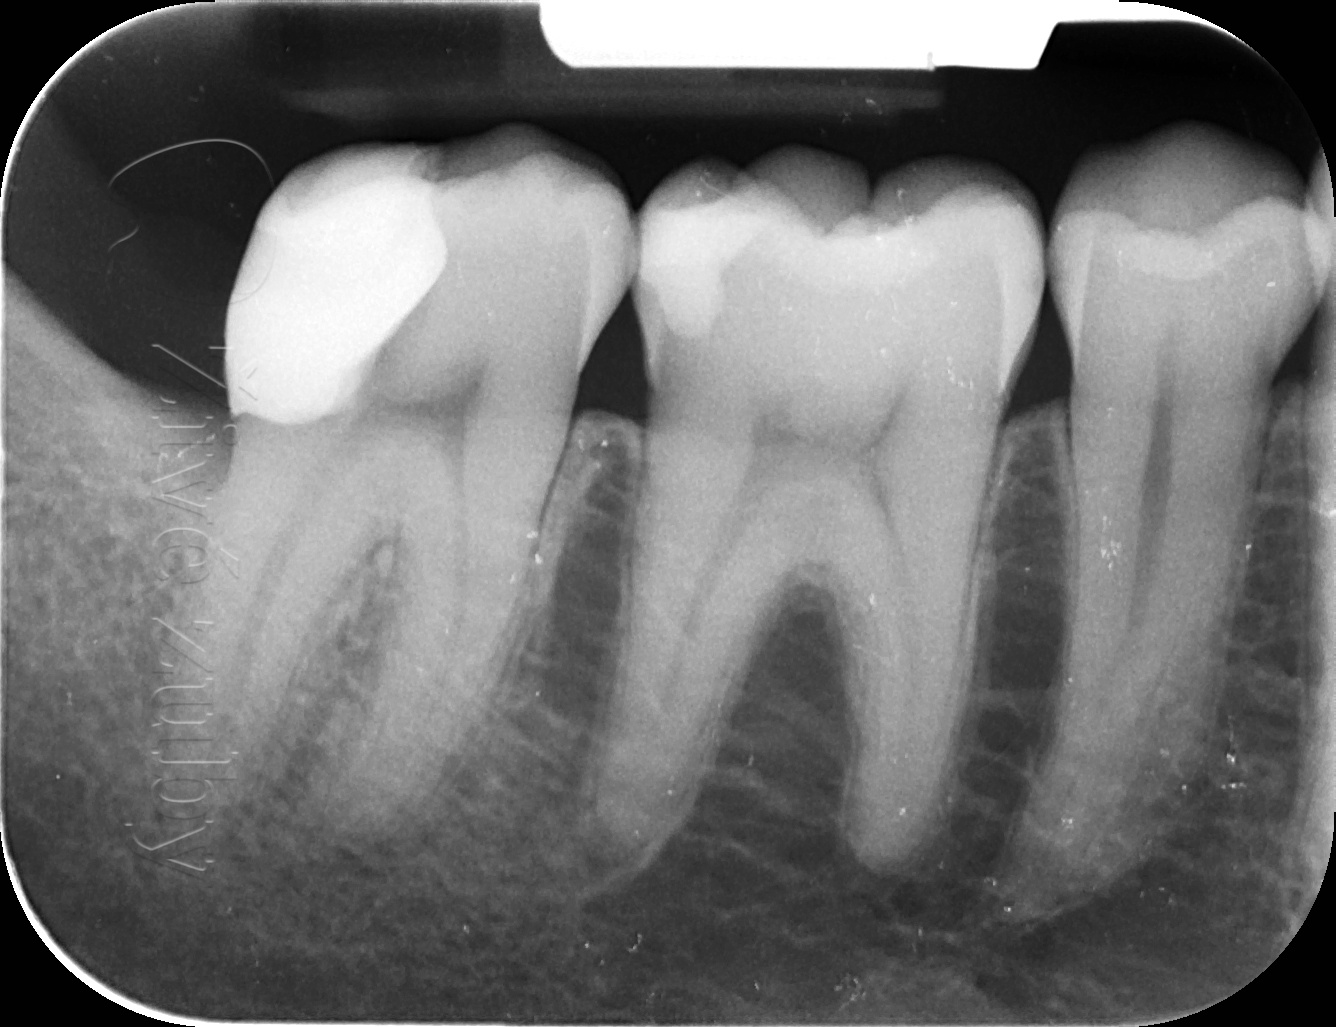

Ošetření hlubokých kazů

Výchozí stav  ——-> Kontrola po 2 letech ——--> Kontrola po 3 letech